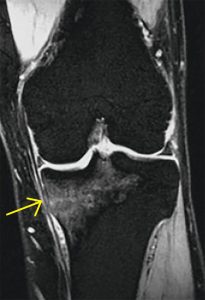

Se puede sospechar el diagnóstico al examinar al paciente y escuchar su historia clínica, Las Rx en algunas ocasiones pueden mostrar la lesión, pero generalmente pasan desapercibidas en los primeros días de los síntomas. La RESONANCIA MAGNÉTICA es el exámen más preciso que puede revelar la lesión y confirmar el diagnóstico que se sospecha.